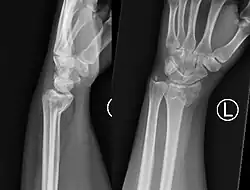

Uma fratura de Smith, também conhecida como fratura de Colles invertida é uma fratura do rádio distal causada por queda sobre punhos fletidos, ao contrário da fratura de Colles, que ocorre em queda sobre punho estendido.